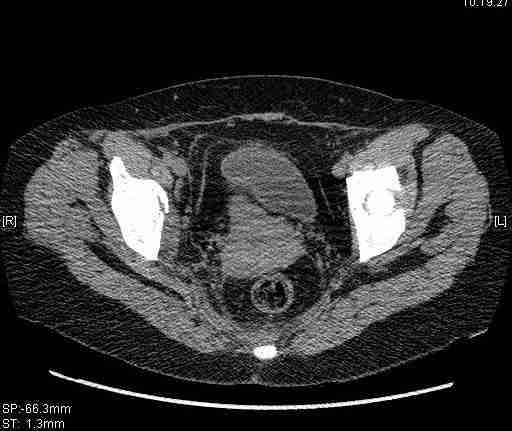

Женщина,58 лет, после ДТП 6 суток. Первично повреждение расценено как переломы ветвей лонной кости. После подтверждения повреждения вертлужной впадины,как чаще всего случается, вопрос встал о тактике. БОльшинство за консерватиное лечение.К сожалению кт у нас "во время" сломался. Прилагаю стандартные снимки вертлужки. У меня следующие вопросы к коллегам:1. Правильно ли рассценивать это повреждение как Т-образный перелом вертлужнй впадины?2. Можно ли добиться анатомической репозиции поверхности вертлужной впадины скелетным вытяжением в данном случае, если нет, что будет этому препятствовать?3. Если смещение останется таким как сейчас, через какое время появится необходимость эндопротезирования (по вашему опыту)?Спасибо.

имеется передний подвывих, головка нагружаемой зоной будет "тереться" о край фрагмента, связанного с осевым скелетом.

Удалось сегодня вывести пациентку в соседнюю больницу, где есть кт. Срезы сделаны только горизонтальные.

|